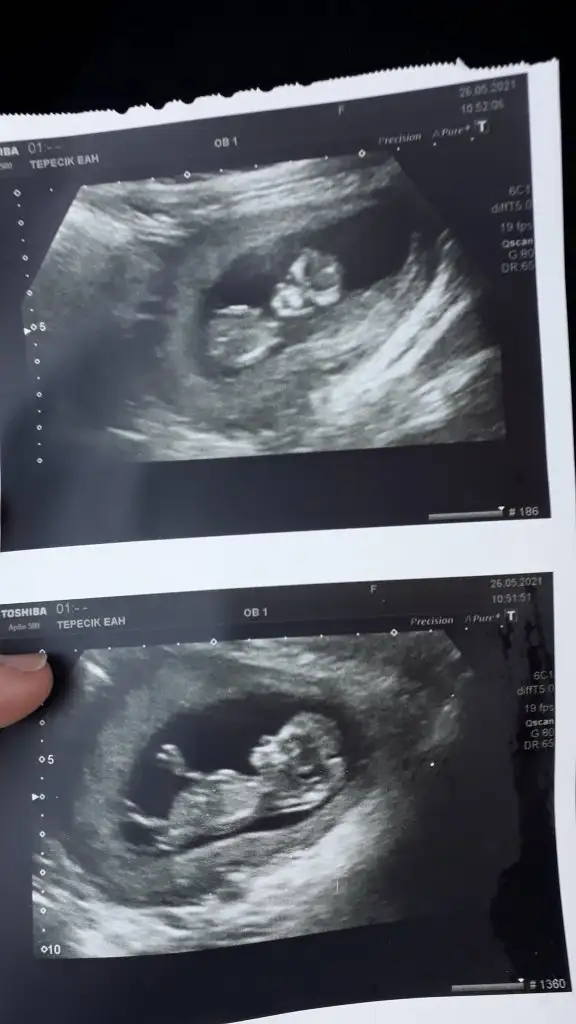

Benim ikizlerim için de yorum yapar mısınoz lütfen

Eklentiler

• 746C7BC3-1586-4531-B197-9DB6AF15268D.webp

19 KB · Görüntüleme: 624

• E4E1986A-49FE-426F-A05A-924C68C1DA1F.webp

17,8 KB · Görüntüleme: 363

• 666239E1-F396-43DE-8A3E-FCAAB945364A.webp

26,1 KB · Görüntüleme: 378